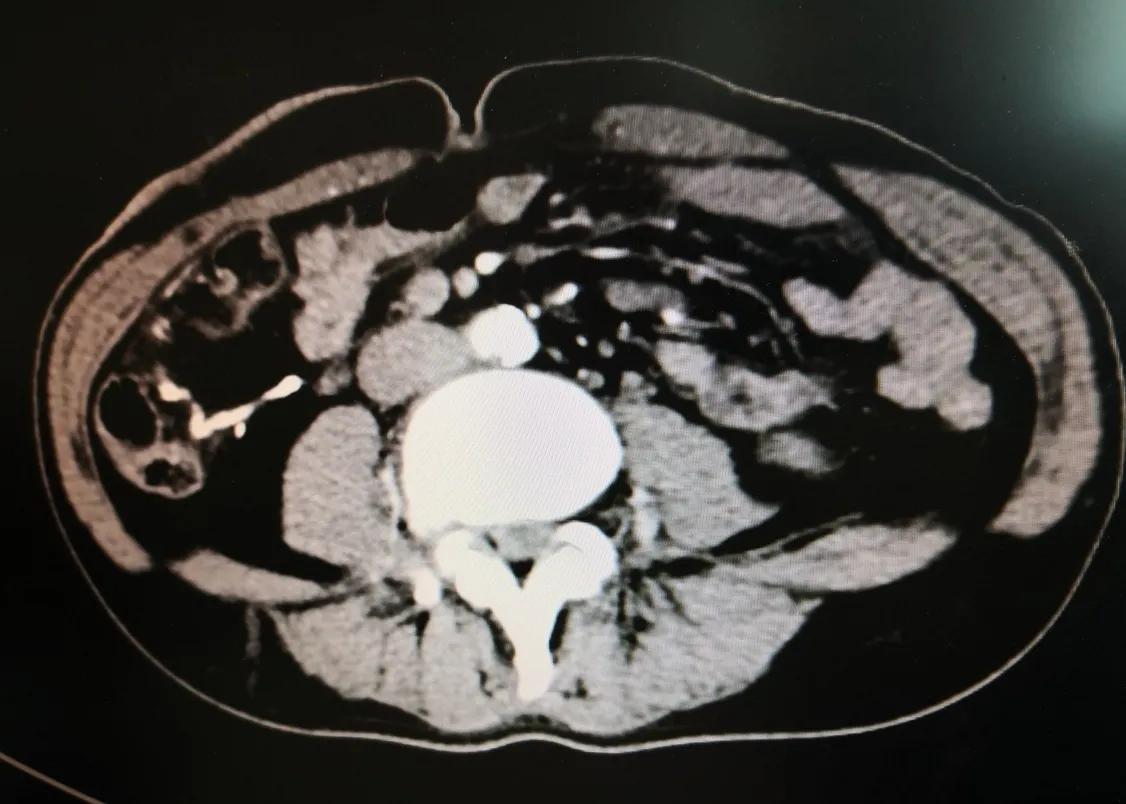

术后复查CT